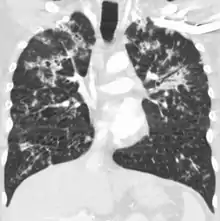

CT, 16 days after onset, showing extensive pulmonary parenchymal involvement consisting of irregular septal thickenings with ground-glass areas and centrilobular nodules with a peri-lymphatic distribution